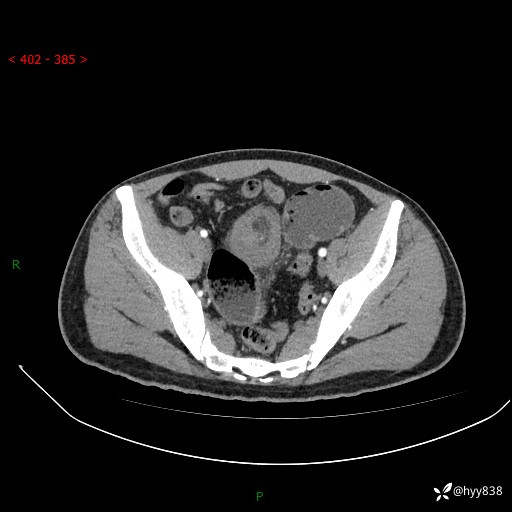

年轻男性,腹痛5月余。除了肠梗阻,你还能看到什么---结果公布~

现病史:患者于5月前无明显诱因开始出现腹痛,上明显,为间断性胀痛不适,无畏寒发热,无心慌气促等特殊不适,遂来我院。我院门诊遂以“腹痛原因待查”收入我科。 起病以来,患者精神、饮食、睡眠欠佳,大小便正常。体力体重无明显变化。

腹部CT增强扫描(动脉期+静脉期)